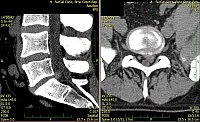

1. Žena, 48 let. Na MR patrná 8mm velká paramediální hernie L5/S1 vlevo s extruzí materiálu ploténky do epidurálního prostoru a útlakem kořenů L5 a S1 vlevo. Pacientce byla doporučena operace, kterou odmítla a zvolila alternativní postup s aplikací ozonu. Viz obr. 6a

Na kontrolním MR po 1 měsíci (po 2 aplikacích ozonu) periradikulárně je viditelné vymizení fragmentů v epidurálním prostoru a částečná retrakce meziobratlové ploténky. Subjektivně výrazná úleva, po 4 týdnech návrat do práce. Viz obr. 6b